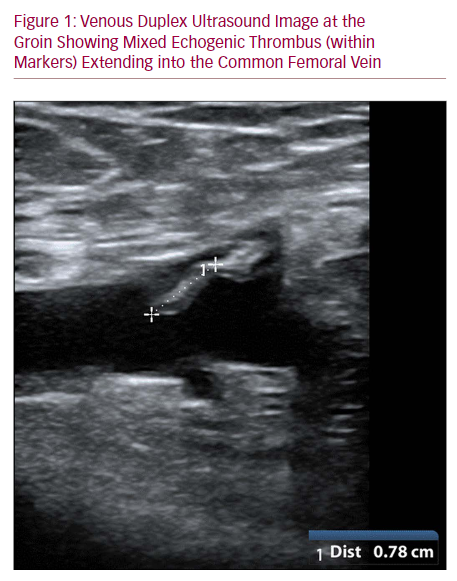

Endovenous glue ablation for lower limb varicose veins is gaining traction due to its proven safety and efficacy. A significant concern, however, is the extension of glue-associated thrombus into deep veins. This article presents a case where thrombus extended into the common femoral vein post endovenous glue ablation for varicose veins using the VenaSeal™ closure system (VCS; Medtronic). A 63-year-old male, presenting with symptomatic varicose veins and saphenofemoral junction incompetence, underwent the VCS closure. A month later, while varicosities showed improvement, an ultrasound revealed thrombus extending into the common femoral vein. This was managed with surveillance duplex and serial clinical observation, showing spontaneous resolution at 12 months. As the use of VCS for varicose veins increases, it's anticipated that thrombotic complications in the deep veins will be encountered more frequently, necessitating the formulation of guideline-based management for this complication.